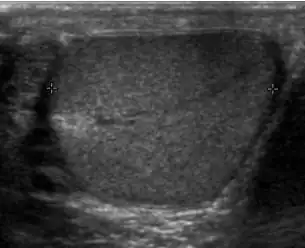

Patients with testicular lymphoma are usually old aged around 60 years of age, present with painless testicular enlargement and less commonly with other systemic symptoms such as weight loss, anorexia, fever and weakness. Bilateral testicle involvements are common and occur in 8.5% to 18% of cases. At sonography, most lymphomas are homogeneous and diffusely replace the testis [Fig. 7]. However focal hypoechoic lesions can occur, hemorrhage and necrosis are rare. At times, the sonographic appearance of lymphoma is indistinguishable from that of the germ cell tumors [Fig. 8], then the patient's age at presentation, symptoms, and medical history, as well as multiplicity and bilaterality of the lesions, are all important factors in making the appropriate diagnosis.